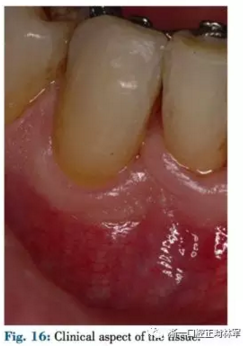

患者42-43區(qū)有復(fù)發(fā)性膿腫,42為兩壁骨袋,遠(yuǎn)中牙周探診9mm(圖12),43探診提示有附著喪失但較穩(wěn)定。患者要求治療膿腫并排齊下頜牙列,因此決定通過(guò)拔除42解決擁擠。方案不采用GTR保留牙齒,通過(guò)正畸拔除42改造骨缺損形態(tài),獲得軟硬組織,避免拔牙區(qū)由于組織的萎縮出現(xiàn)不美觀的裂口。通過(guò)鄰牙的擠壓重建生理性鄰間解剖結(jié)構(gòu)?;颊呤褂蒙鄠?cè)粘接,初期通過(guò)牽引42,43以排齊并修復(fù)43近中骨缺損。隨后緩慢牽引42,42處加轉(zhuǎn)矩扭轉(zhuǎn)牙以增加頰側(cè)骨量并減少軟組織塌陷,避免后期拔牙由于骨皮質(zhì)薄導(dǎo)致的裂縫,先用0.016TMA后用0.017×0.017帶鉤TMA完成(圖13-16)。